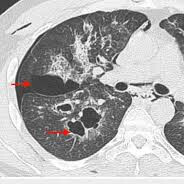

Pulmonary blebs are small subpleural air-filled circumscribed cystic spaces, usually less than 1 cm in diameter. There is an association with small airways disease. Rupture causes pneumothorax and is associated with tobacco smoking.

Blebs are thought to occur as a result of subpleural alveolar rupture, due to strain overload of the elastic fibers.

Pulmonary bullae are, like blebs, cystic air spaces that have an imperceptible wall (less than 1 mm). Bullae are typically larger but there is no size cut-off to distinguish bullae from blebs. Blebs may, over time, coalesce to form bullae.

The smallest blebs are not visible on imaging but can be detected in pathological specimens.